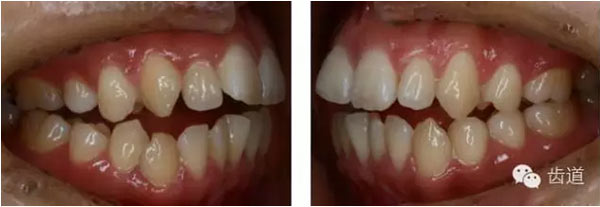

—前牙開(kāi)合

—前磨牙區(qū)及前牙區(qū)均為開(kāi)合

—右側(cè)自第一磨牙開(kāi)始至側(cè)切牙均為反合

Spee曲線1.5mm;前牙開(kāi)合3mm;深覆蓋4mm

矯治結(jié)束后口內(nèi)像

治療前后口內(nèi)相對(duì)比